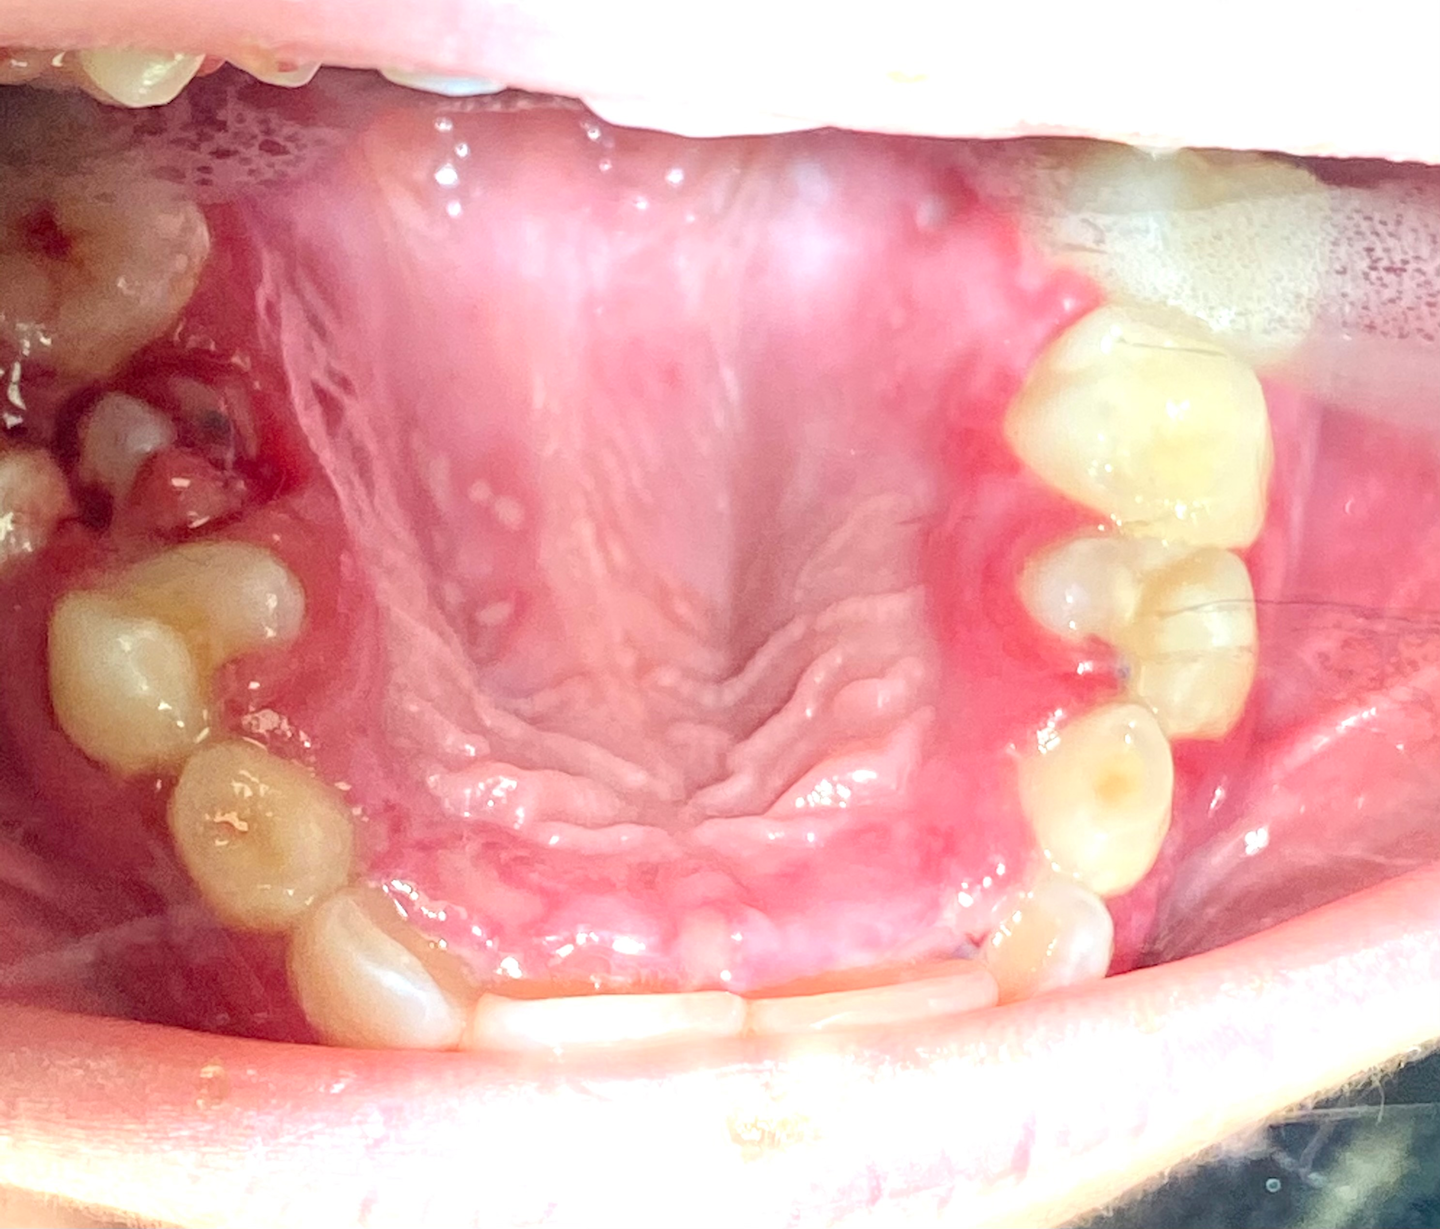

Mengenai keluhan utama pasien, berikut adalah gambaran klinisnya (gambar 3–8):

- Durasi gejala adalah sekitar satu minggu.

- Pasien mengalami malaise umum tetapi masih optimis dan dalam semangat yang baik.

- Seperti yang disebutkan dalam pendahuluan, itu menyakitkan bagi pasien untuk menelan, membuka, dan menggerakkan lidahnya; nafsu makannya berkurang karena rasa sakit dan ketidakmampuan untuk memasukkan apa pun ke dalam mulut atau mengunyahnya.

- Lesi berkrusta yang hadir di perioral dan hidung proximities.

- Intraoral, terdapat ulserasi oral multipel yang tersebar dengan gambaran lesi putih yang dikelilingi oleh dasar eritematosa pada permukaan dorsal dan ventral lidah; langit-langit keras dan lunak juga tertutup.

- Beberapa lesi tampak menyatu.

- Jaringan gingiva adalah merah, meradang, dan berdarah pada sentuhan sekecil apa pun.

- Sejumlah sedang plak melapisi gigi; beberapa gigi sulung lepas dengan gigi dewasa yang erupsi.

- Ada bau busuk pada napas pasien.

- Limfadenopati ringan diamati di kelenjar submandibular dan daerah leher.